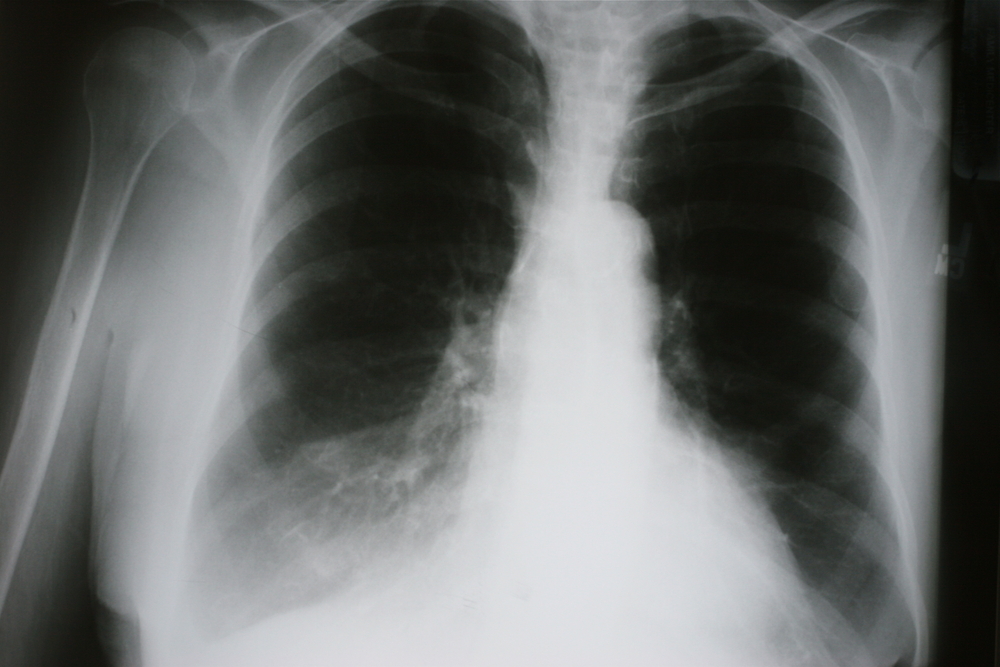

- Рентгенография легких в двух (прямой и боковой) проекциях. Будет обнаружено однородное затемнение участка легочного поля, смещение в сторону поражения средостения, высокое стояние купола диафрагмы с пораженной стороны. Здоровое легкое с повышенной воздушностью.

- Рентгеноскопия легких. Важен характер смещения органов средостения при дыхании: для ателектаза характерно смещение их в сторону поражения на вдохе, а на выдохе и при кашле – в противоположную сторону.

- Компьютерная томография легких. Назначается в тяжелых, сомнительных случаях. Позволяет визуализировать даже маленькие ателектазы.